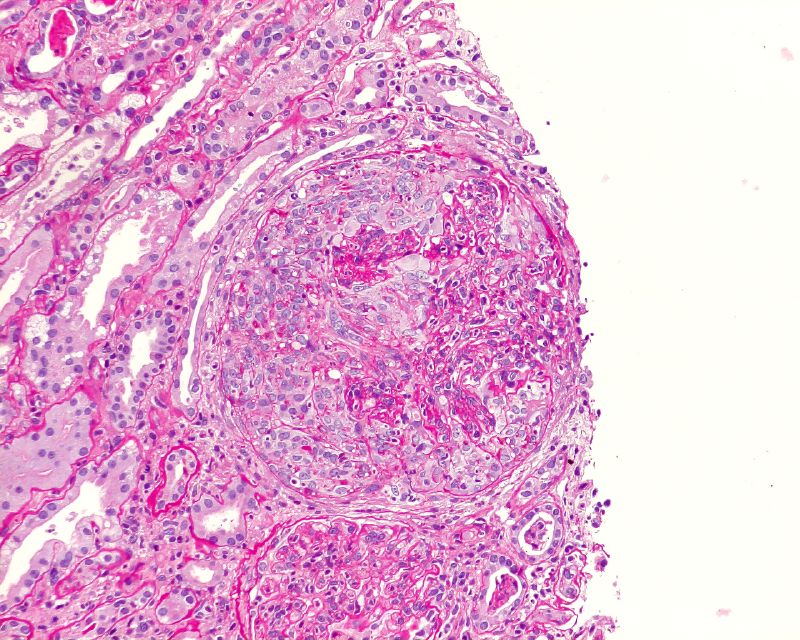

| Large cellular crescent in a patient with post-infectious glomerulonephritis; neutrophils visible in glomerular tuft. (Boonyarit Cheunsuchon, Mahidol University, Bangkok (Creative Commons licence) |